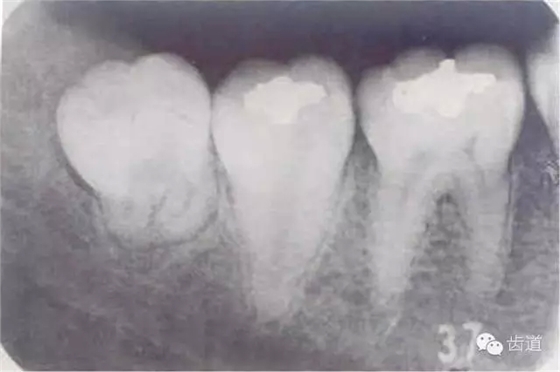

下頜第三磨牙在萌出過程中,由于萌出不全或阻生,牙冠周圍軟組織發(fā)生的炎癥。又稱智齒冠周炎。

1.人類進(jìn)化過程中,下頜骨體逐漸縮短,導(dǎo)致第三磨牙萌出空間不足,表現(xiàn)為部分萌出、牙位偏斜甚至完全埋伏阻生

2.冠周齦瓣形成盲袋,食物殘?jiān)M(jìn)入后不易清除,細(xì)菌在此生長(zhǎng)繁殖

3.雙向受力,局部血運(yùn)差,細(xì)菌入侵

1.智齒萌出不全

2.牙冠周圍軟組織紅腫、糜爛、觸痛

3.齦瓣處形成盲袋,內(nèi)有膿性分泌物,有時(shí)形成冠周膿腫

4.嚴(yán)重時(shí)可見咽側(cè)壁及舌腭弓紅腫,患側(cè)頜下淋巴結(jié)腫大、壓痛。